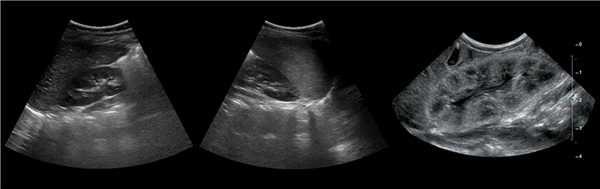

• Серошкальное УЗИ:

о Гомогенное округлое образование, изоэхогенное корковому веществу почки

о Расположена между почечными пирамидами

о Нормальные контуры почки

о Ограничена гиперэхогенной линией соединительной паренхимы и гиперэхогенным треугольным дефектом соединительной паренхимы

о Вдается в почечную пазуху с латеральной стороны

о Гиперэхогенность может быть обусловлена анизотропией

• Цветовая допплерография:

о Нормальная перфузия указывает на неизмененную почечную ткань

о Отсутствует деформация сосудов с нормальными дугообразными артериями, окружающими пирамиды

о Отсутствуют аномальные сосуды

(Левый) На рисунке показана бертиниева колонна, которая является не истинным новообразованием, а разрастанием коркового вещества почки между пирамидами.

(Правый) На продольном ультразвуковом срезе правой почки визуализируется гипертрофированная колонна Бертена, вдающаяся в клетчатку почечной пазухи в среднем отделе почки. Обратите внимание на ее изоэхогенность корковому веществу и гладкие наружные контуры.